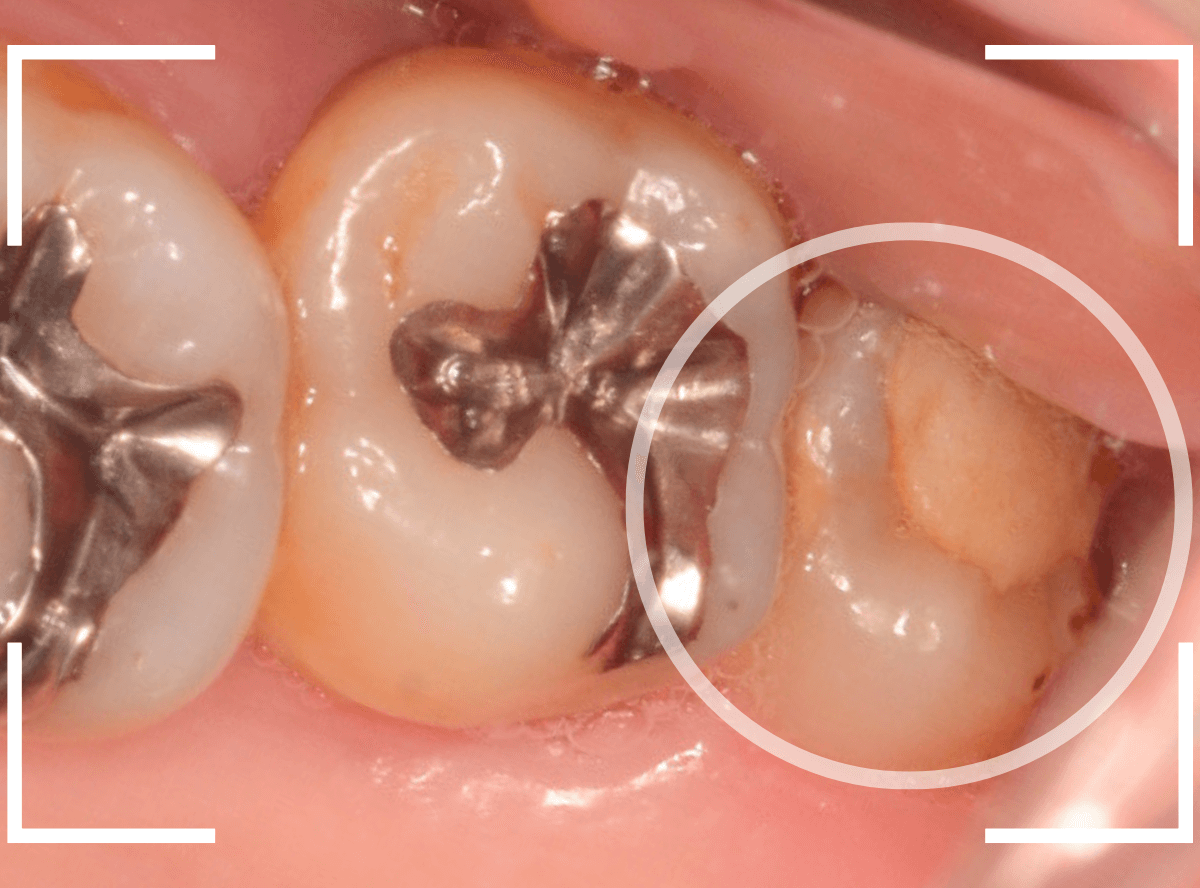

今回は、上のおやしらずが原因で虫歯になってしまった方のケースです。

〇部のおやしらずを虫歯で抜歯しました。

抜歯してしばらく経ったところです。

特に問題なさそうに見えますが、「おやしらずを抜歯してから、歯がしみるようになった」との訴えです。

これは、おやしらずを抜歯した後によくある症状です。